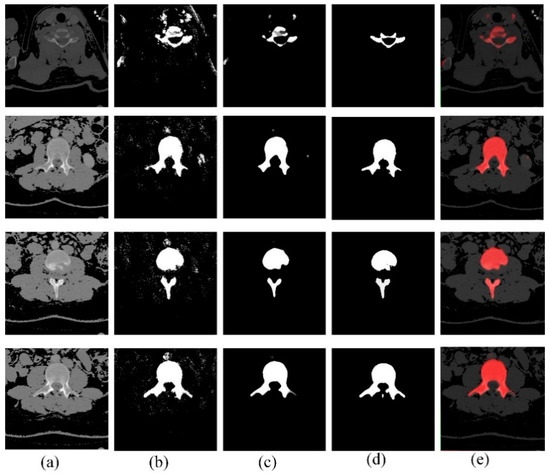

2.1. Preprocessing

2.2. Patch Generation

2.4. Segmentation